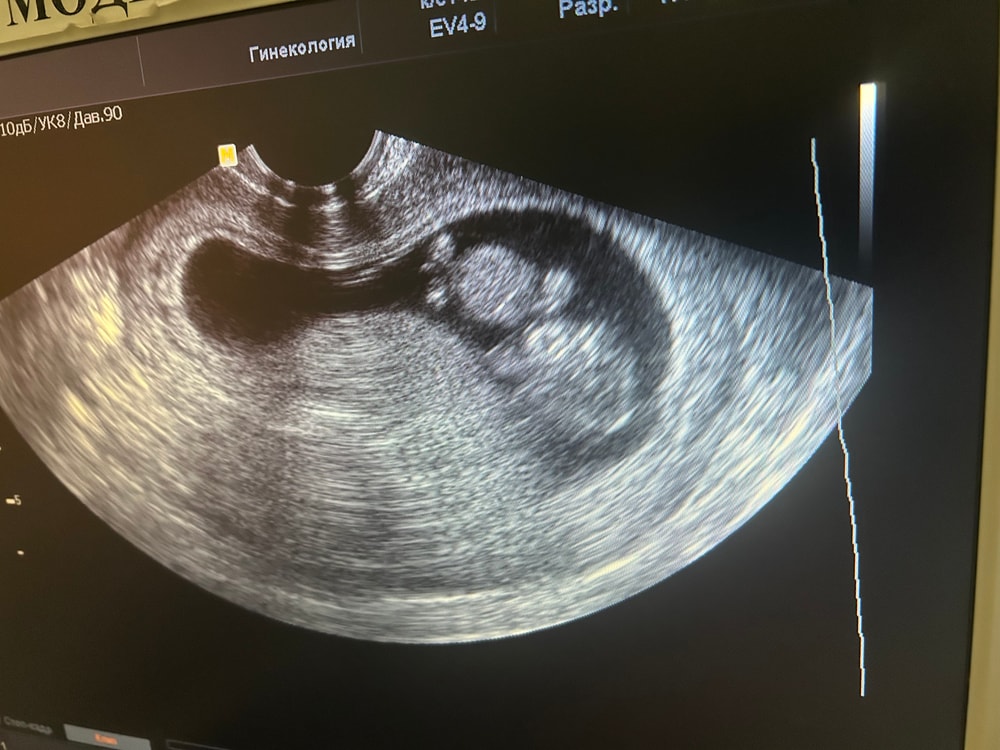

Пол на ранних сроках

На таком сроке еще не различимы половые органы

В 10 нед нельзя определить. У меня на скрининге срок 12+4, по ктр 13 нед врач, очень опытный узист, смотрела во всех ракурсах очень пристально и долго, и смогла точно увидеть, сказала четко видно - мальчик. На таком-то сроке это не так просто, а в 10 только начинает формироваться половой бугорок, соответственно увидеть пол нереально.

Мне примерно с таким же снимком врач узи сказала : «Девочку ждете ?» А я внутри так возмутилась на тот момент , не знаю почему . Но видно она хотела свои великолепные знания в методе Рамзи или еще каком продемонстрировать, но не вышло 😂. Так что даже врачи по этим узи ошибаются .

По крови если только. По узи информативно после 14-15 недели, тк даже на 13й с хорошим аппаратом у нас ошибались. В 10 там толком нет еще ничего.

Они еще все «одного» пола)))

Ksenia Seven, да) но на вашем узи не видно, качество плохое, да и я не умею определять по этим фотографиям. Тут иногда девочки конечно попадаются, которые умеют) набор пятен каких-то, но они понимают. Я нет)

Мария, мне когда врач показала этот кадр, я спросила мол а где что, ибо не сразу сообразила где голова и тд 😆

Пол малыша Половой бугорок, 11 недель